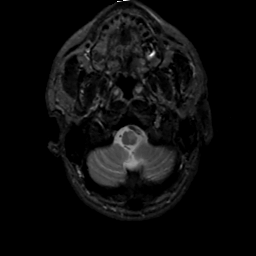

MR Study #2, February 17, 1991 -- Slice #4

[Home][Help][Clinical][Tour 1][Tour 2] Slice 4